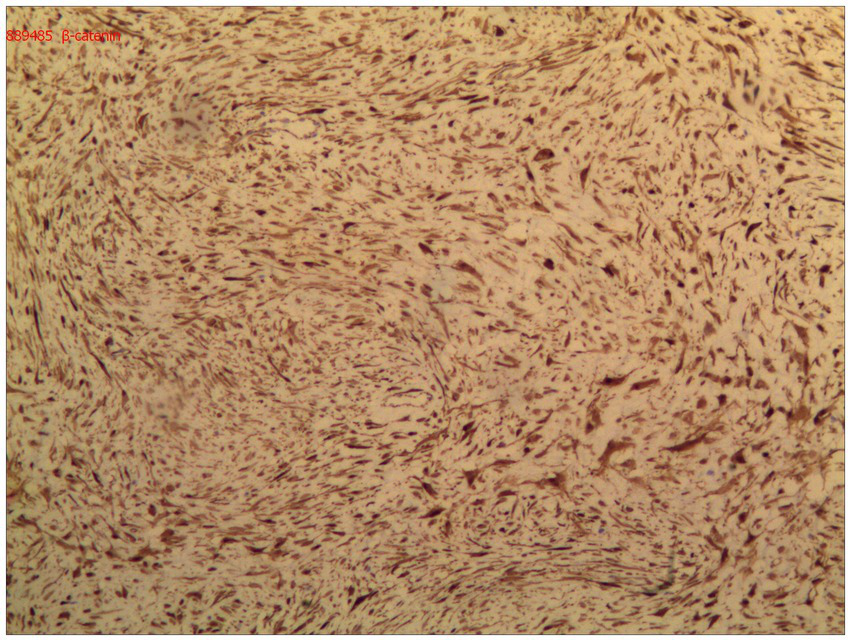

Immunohistochemical analysis demonstrated diffuse nuclear expression of β-catenin (Figure 5), along with nuclear positivity for vimentin (Vim), smooth muscle actin (SMA), and desmin (Des). The mass was negative for CD34, DOG-1, S-100, ENA, actin, and S-100. The final pathological diagnosis confirmed primary DF of the distal ileum (invasive fibromatosis).

DF arises from proliferating myofibroblasts, and the Wnt/β-catenin pathway plays a central role in tumorigenesis (11). Most cases of DF exhibit mutations in the β-catenin gene. This mutation triggers a cascade of reactions that promote cell proliferation and differentiation, leading to DF development.

Macroscopically, DF appears as a firm, grayish-white, scar-like mass. It is characterized by heterogeneous, indistinct, and uniform proliferation of spindle-shaped cells, representing myofibroblasts surrounded by a collagen-rich matrix and lacking a capsule (4). Immunohistochemistry (IHC) assays show nuclear positivity for β-catenin, vimentin, Cox-2, c-KIT, PDGFRb, androgen receptor (AR), and estrogen receptor α (ERα) in DF. However, DF is negative for desmin, S-100, h-caldesmon, CD34, and c-KIT (2).